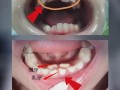

(图片来源网络,侵删) -

精子畸形率增高:这是非常关键的一点,香烟中的化学物质会损害精子DNA的完整性,导致精子头部、颈部等形态异常,畸形精子即使与卵子结合,也容易导致流产、胎停育或胎儿出生缺陷。